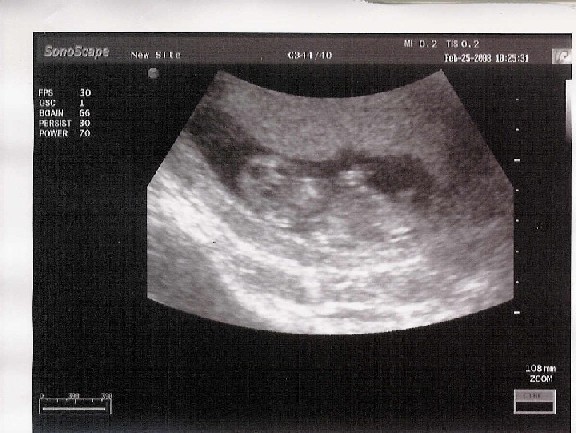

persze, innentôl örökké aggódunk!!! ha megszületnek, onnantól talán jobban is, hiszen addig legalább mindig tudjuk hol vannak, jól vannak lakva, minden oké, le nem eshetnek, senki más nem árthat nekik, stb...ha meg kint vannak, onnan bármi lehet.... de ez így van amióta élôlények vannak, így van rendjén. nem hiába, az anyuka aggódik, ez normális!!

ja és tök jól látszik már a pocak!!! széép

Ez Ő

Kis bernik